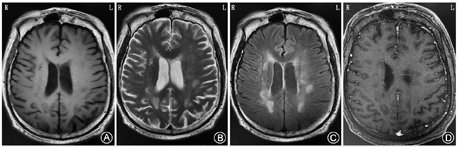

给予患者甲泼尼龙琥珀酸钠冲击,丙种球蛋白,吗替麦考酚酯,鞘内注射甲氨蝶呤。发病4个月后复查,MRI显示:颅内脑质多发异常信号,较前病变范围,程度明显减轻(图4)。认知明显提高,MSE 17分(治疗前8分),MoCA 13分(治疗前2分),画钟检测0分(治疗前0分)。患者能主动开玩笑,可进行简单的生活自理,可简单购物等。